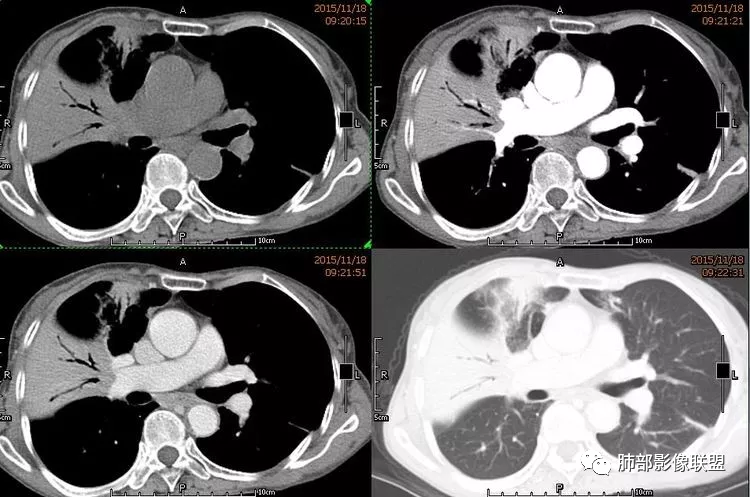

病变分布特点,胸膜下,叶间胸膜下为主,呈大小不等结节级团块影,部分病灶内见支气管影,病灶收缩不明显,从分布及慢性发病看,隐球和淋巴瘤都可,补充增强,病灶内见血管穿行,强化不明显,支持淋巴瘤

老年男性,两肺多发结节肿块,胸膜下分布为主,部分支气管进入闭塞,增强扫描有强化,血管穿行无破坏,边缘尚光滑,周围无晕,病灶整体膨隆为主,半年病程,症状逍遥,首先考虑淋巴瘤

棉花糖:双肺多大小不等结节,边缘清楚,无毛刺,浅分叶,胸膜下分布为主,内可见支气管穿行,增强后中等程度强化,病灶内血管走行自然,考虑淋巴瘤,鉴别GPA

内部支气管稍扩张,直达远端,或受压变形、移位

均匀强化

内部血管走形自然,稍纤细

2.病灶的密度:密度均匀,部分病灶内可见空洞及气液平,轻中度均匀强化。

MALT--密度均匀、轻中度强化

4.血管造影征:肿瘤组织浸润引起间质增厚、肺泡壁破坏、肺泡腔充填,而周围充盈血管走行自然,未受肿瘤侵犯。血管造影征